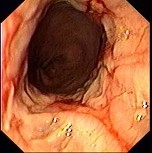

(单选题)胃镜检查如下图,诊断为()。

A:食管癌

B:反流性食管炎

C:心绞痛

D:消化性溃疡

E:贲门癌